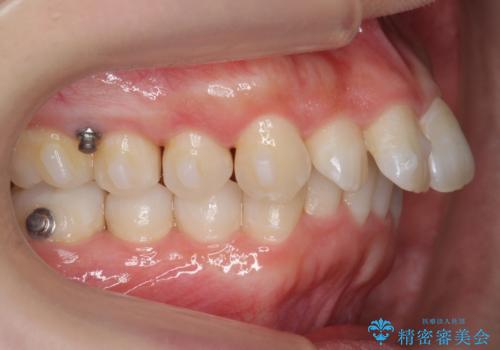

前歯をさげたい 歯を抜かずに マウスピース矯正で治したい

- 上の前歯が出ているとのことで来院。

歯を抜かずに、上の奥歯を後ろにさげつつ上の前歯を小さく少し削る処置を行い前歯の角度を修正しました。

右上下の奥歯もすれ違い咬合も、治療で改善しています。

- 104.5万円(マウスピース矯正 93.5万円、矯正用スクリュー11万円)費用は治療当時の料金となります